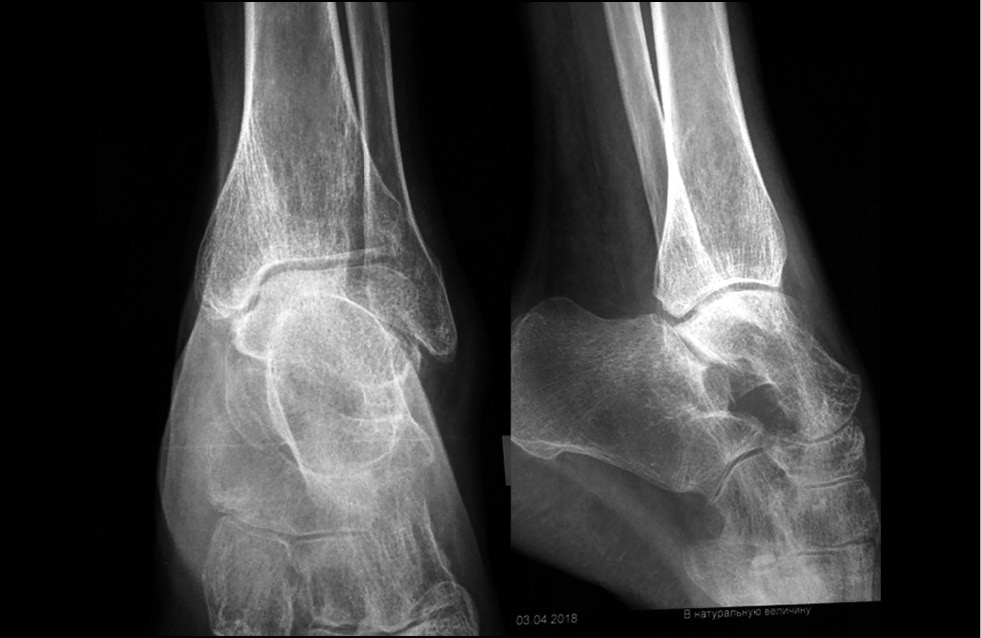

Рис. 2. Рентгенограммы, фиксирующие порочное положение стоп и голеностопных суставов, остеопороз, подвывихи в таранно-ладьевидных суставах

Fig. 2. Radiographs presenting the vicious position of feet and ankle joints, osteoporosis, talonavicular joints subluxation